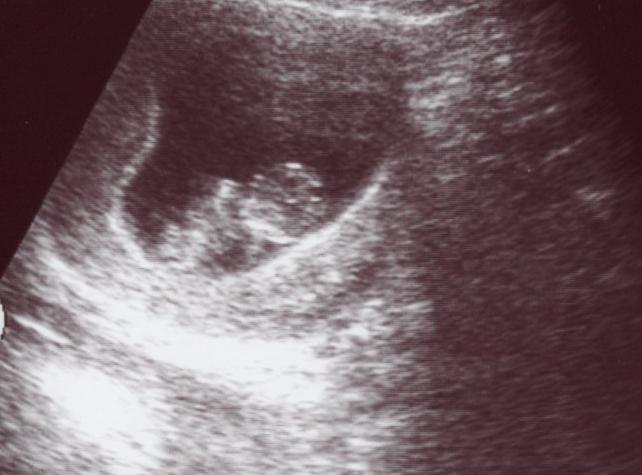

仕事の都合で9w0dには行けず、今日になってしまった。

今、大体3ヶ月半目。